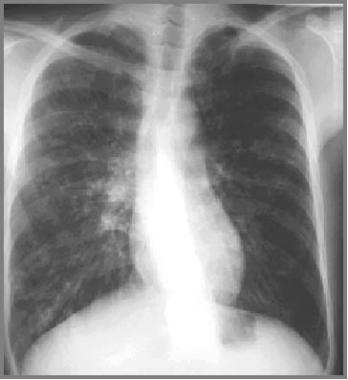

患有轻度肺部疾病的囊性纤维化患者的胸片可能正常。由于黏液堵塞而导致的肺部过度充气可能是儿童或成人时期的唯一表现。

中度或晚期时的肺部可能出现线状阴影和散在结节,并可能观察到节段性、斑片性或小叶性肺不张,儿童比成人更为多见,通常表现在右上叶。

图1 患囊性纤维化的青年男性,显示过度充气和上叶支气管扩张。

图3 囊性纤维化患者双侧支气管扩张,并伴有左上叶肺不张

图5 27岁患者仅有轻微症状,显示为支气管壁增厚、双侧小结节状浑浊和脊柱侧弯。